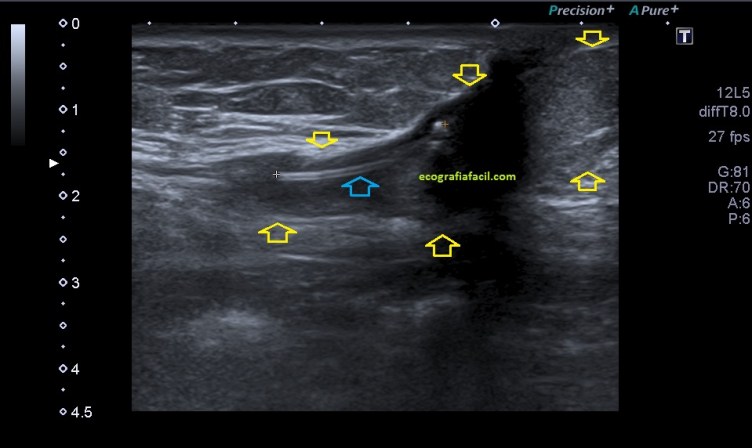

En ocasiones, como en la imagen superior, el seroma, convertido en absceso por la presencia de material quirúrgico que quedó en la herida quirúrgica. La colección se torna en hipoecogénica, flanqueado por flechas amarillas, el cuerpo extraño, que un trozo de drenaje que quedó atrapado al extraerlo está marcado por una flecha azul y medido, siendo su ecoarquitectura, hiperecogénica, curva y tubular.